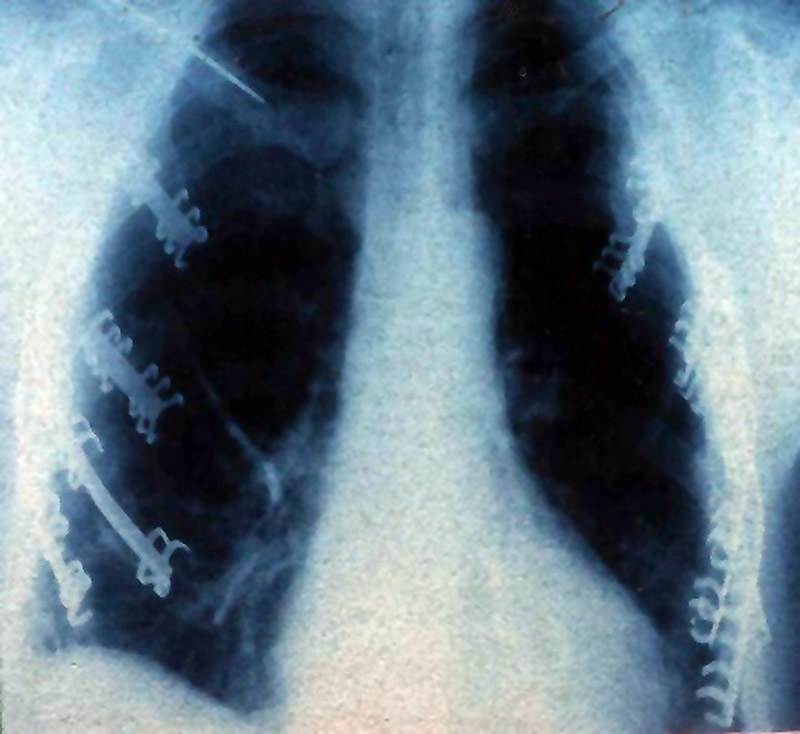

Figure 11. Triple drained pleural space with a supplemental smaller drainage catheter in the subcutaneous plane. Figure 12. Postoperative chest x-ray of a patient who underwent surgical stabilization of bilateral flail chest (antero-posterior).

Patients who undergo surgical fixation of a flail chest should be gradually weaned from the ventilator in order to prevent early displacement of the fixed ribs. In our experience mechanical ventilation is usually continued for 36 to 48 hrs postoperatively. The patient is discharged after radiographs (Figure 12) show resolution of traumatic pleuro-pulmonary injuries and after clinical evaluation demonstrates the absence of paradoxical movement of the chest wall. The metal plates do not need to be removed after healing has occurred.